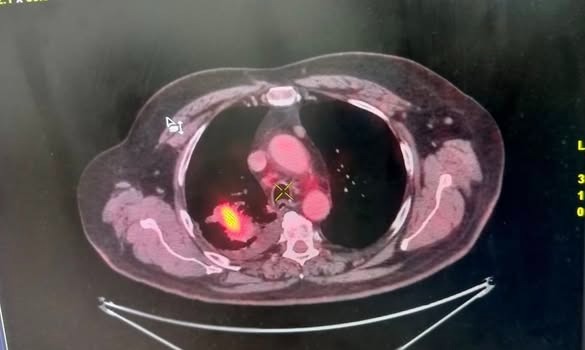

नोएडा में 9 अक्टूबर 2025 को फोर्टिस नोएडा ने फेफड़ों की कोन बीम सीटी (सीबीसीटी) निर्देशित क्रायो बायोप्सी सफलतापूर्वक करके उत्तर भारत में चिकित्सा जगत में पहली बार एक उपलब्धि हासिल की है। इस अत्याधुनिक प्रक्रिया से डॉक्टरों को एक 70 वर्षीय मरीज में फेफड़ों के कैंसर का निदान करने में मदद मिली, जिसकी स्थिति शहर के कई अन्य अस्पतालों में कई परीक्षणों के बावजूद पता नहीं चल पाई थी। यह मरीज, जो लंबे समय से धूम्रपान करता था, सांस लेने में तकलीफ और तेजी से वजन घटने की शिकायत के साथ फोर्टिस नोएडा आया था। अन्य अस्पतालों में की गई पिछली जाँचें अनिर्णायक थीं, जिनमें केवल संक्रमण या अस्पष्ट निष्कर्षों का संकेत मिला था। फोर्टिस नोएडा में एक पीईटी सीटी स्कैन से फेफड़े में एक संदिग्ध घाव का पता चला। हालाँकि, फेफड़े में छेद होने के उच्च जोखिम और अपर्याप्त या गैर-निदानात्मक नमूने प्राप्त होने की संभावना के कारण मानक बायोप्सी विधियों को खारिज कर दिया गया था,

इस मामले में कई नैदानिक चुनौतियाँ सामने आईं - ब्रोंकोस्कोपी और द्रव विश्लेषण सहित पहले के परीक्षण, अंतर्निहित कारण की पहचान करने में विफल रहे थे। यहाँ तक कि सीटी-निर्देशित बायोप्सी और रेडियल ईबीयूएस को भी अनुपयुक्त माना गया क्योंकि फेफड़े का अधिकांश भाग परिगलित (मृत ऊतक) दिखाई दे रहा था, जिससे व्यवहार्य ट्यूमर क्षेत्रों को अलग करना मुश्किल हो गया था।

इन चुनौतियों से निपटने के लिए, फोर्टिस नोएडा पल्मोनोलॉजी टीम ने, जिसका नेतृत्व पल्मोनोलॉजी के अतिरिक्त निदेशक डॉ. राहुल शर्मा कर रहे थे, सीबीसीटी-निर्देशित क्रायो-लंग बायोप्सी का विकल्प चुना, जो एक अगली पीढ़ी की, न्यूनतम आक्रामक तकनीक है जो बेहतर परिशुद्धता के लिए रीयल-टाइम 3डी इमेजिंग, उन्नत स्कोप नेविगेशन और संवर्धित फ्लोरोस्कोपी का संयोजन करती है। इस दृष्टिकोण ने टीम को क्षतिग्रस्त या परिगलित क्षेत्रों से बचते हुए फेफड़े के द्रव्यमान के जीवित भाग से सुरक्षित रूप से अक्षुण्ण ऊतक के नमूने निकालने में सक्षम बनाया।

बायोप्सी ने नॉन-स्मॉल सेल कार्सिनोमा - फेफड़ों के कैंसर का एक प्रकार - की उपस्थिति की पुष्टि की और अतिरिक्त लिम्फ नोड नमूने से कैंसर के प्रारंभिक प्रसार का पता चला। इस सटीक निदान और अवस्था निर्धारण से डॉक्टरों को अनावश्यक सर्जरी और देरी से बचने के लिए तुरंत सही उपचार योजना शुरू करने में मदद मिली।